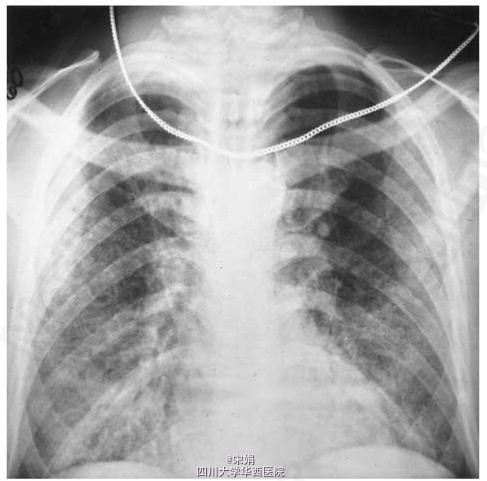

41岁男性,HIV携带者,发热、咳嗽、进行性加重呼吸困难4月就诊。胸片可见弥漫性、双侧胸部网状结节影。

支气管肺泡灌洗最后确诊,发现小的、出芽酵母样组织胞浆菌。 病人予以插管、两性霉素B治疗,插管及治疗后第六天患者体温回复正常,胸片可见肺野清晰。三天后葡萄球菌败血症进展,患者死于急性脑血管事件。